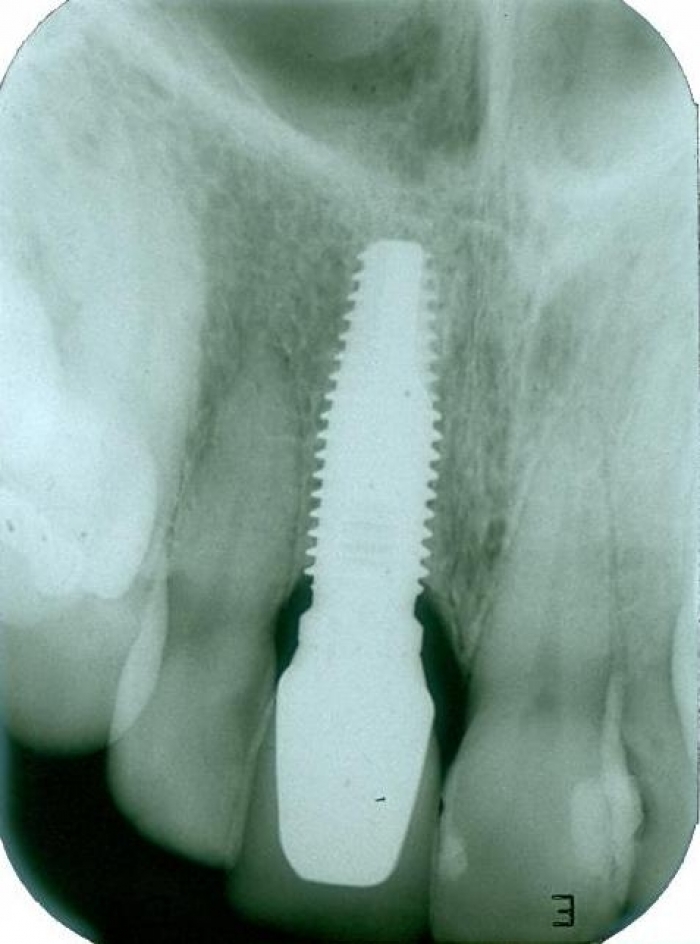

Rx do implante com a prótese instalada.